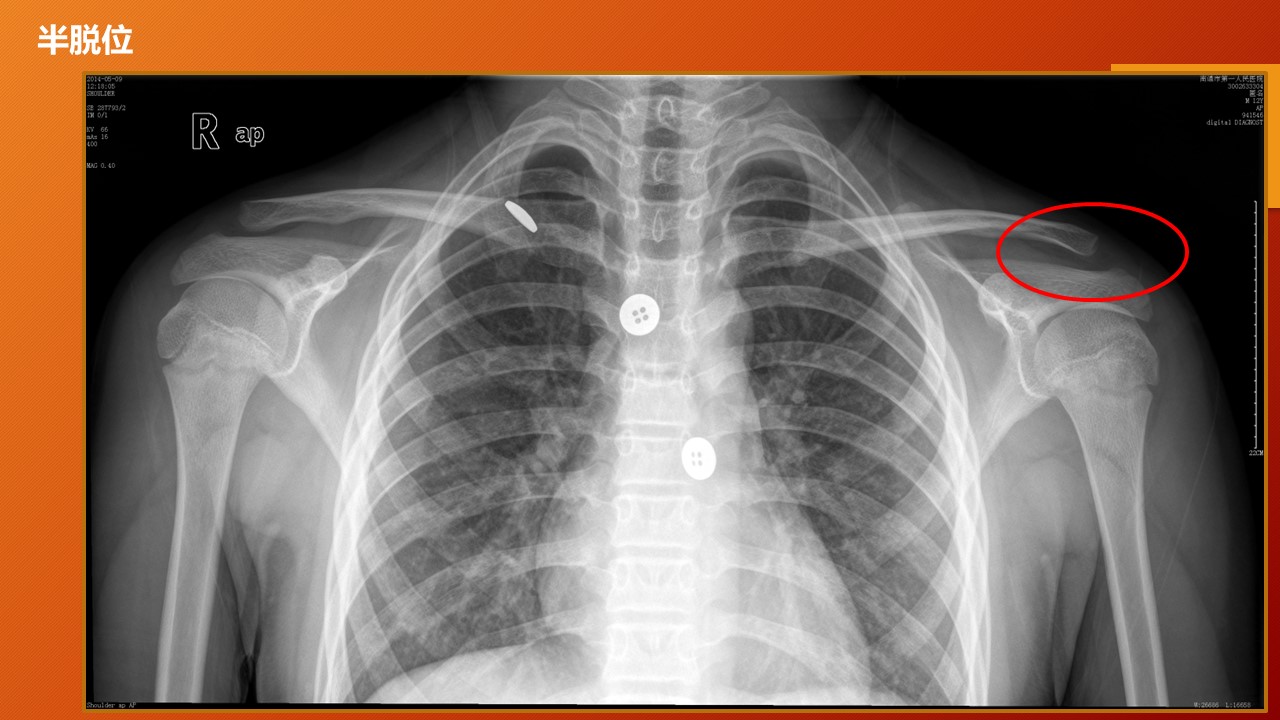

肩锁关节脱位PPT

URIST 形态分型